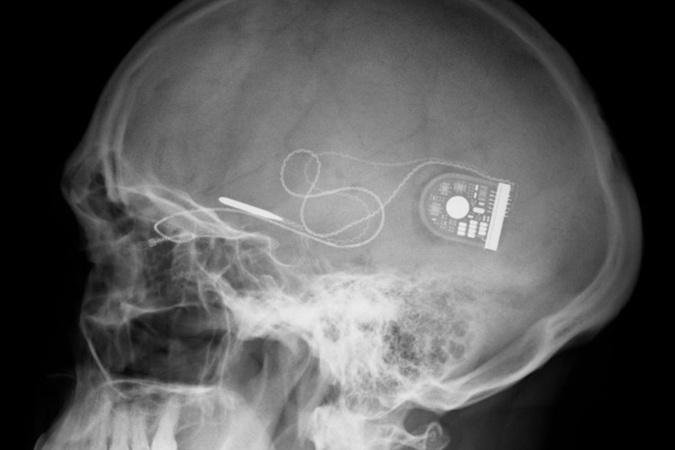

И если раньше импланты были достаточно крупными, то сейчас DARPA хочет уменьшить размеры до размеров нервных волокон. Таким образом, их можно будет имплантировать с минимально инвазивной процедурой (через иглу) и прикрепить к определенным нервным волокнам для очень точной стимуляции.

- В рамках программы ElectRx DARPA планирует разработать технологию, которая может коренным образом изменить способ диагностики, мониторинга и лечения травм и заболеваний. Вместо того чтобы полагаться только на лекарства, мы предвидим систему замкнутого цикла, которая на бумаге будет работать как крошечный интеллектуальный кардиостимулятор. Он будет постоянно оценивать состояние и обеспечивать стимулирование, стремясь сохранить здоровую функцию органа и помочь пациентам оставаться здоровыми и здорово использовать свои собственные тела, - заявил сотрудник DARPA Дуг Вебер.